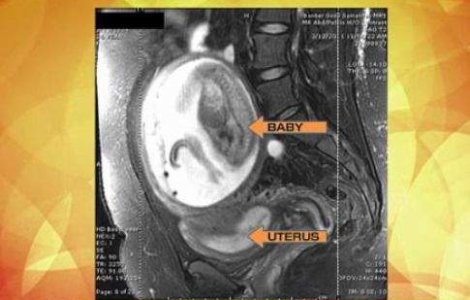

Nu in fiecare zi auzi despre copii care se dezvolta in afara uterului mamei, supravietuiesc nasterii si mai sunt si sanatosi tun, pe deasupra. Insa, cazul unei americance de 27 de ani te lasa cu gura cascata.